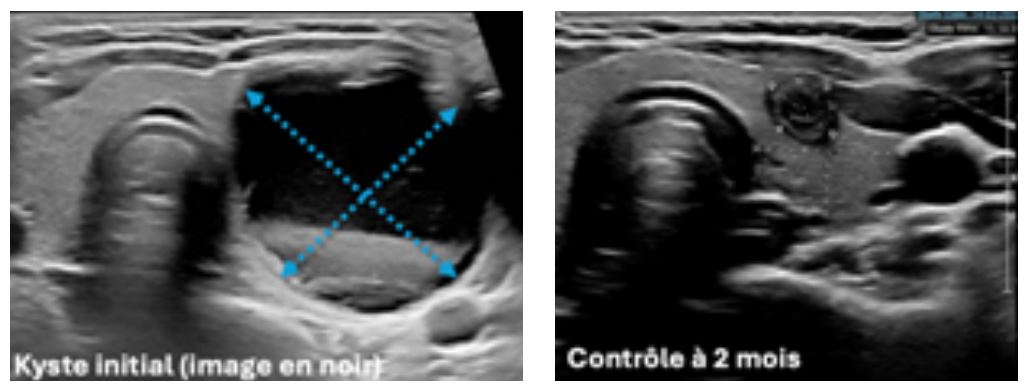

Elles se déroule dans le service de radiologie, l’anesthésie locale (piquer de la peau, comme chez le dentiste) est optionnelle, une aiguille est mise en place, le liquide vidé, puis une faible quantité d’alcool absolu (95%) est injectée par la même aiguille, sous contrôle échographique permanent. L’alcool entraîne une sclérose chimique des parois du kyste et évite qu’il continue à créer du liquide.